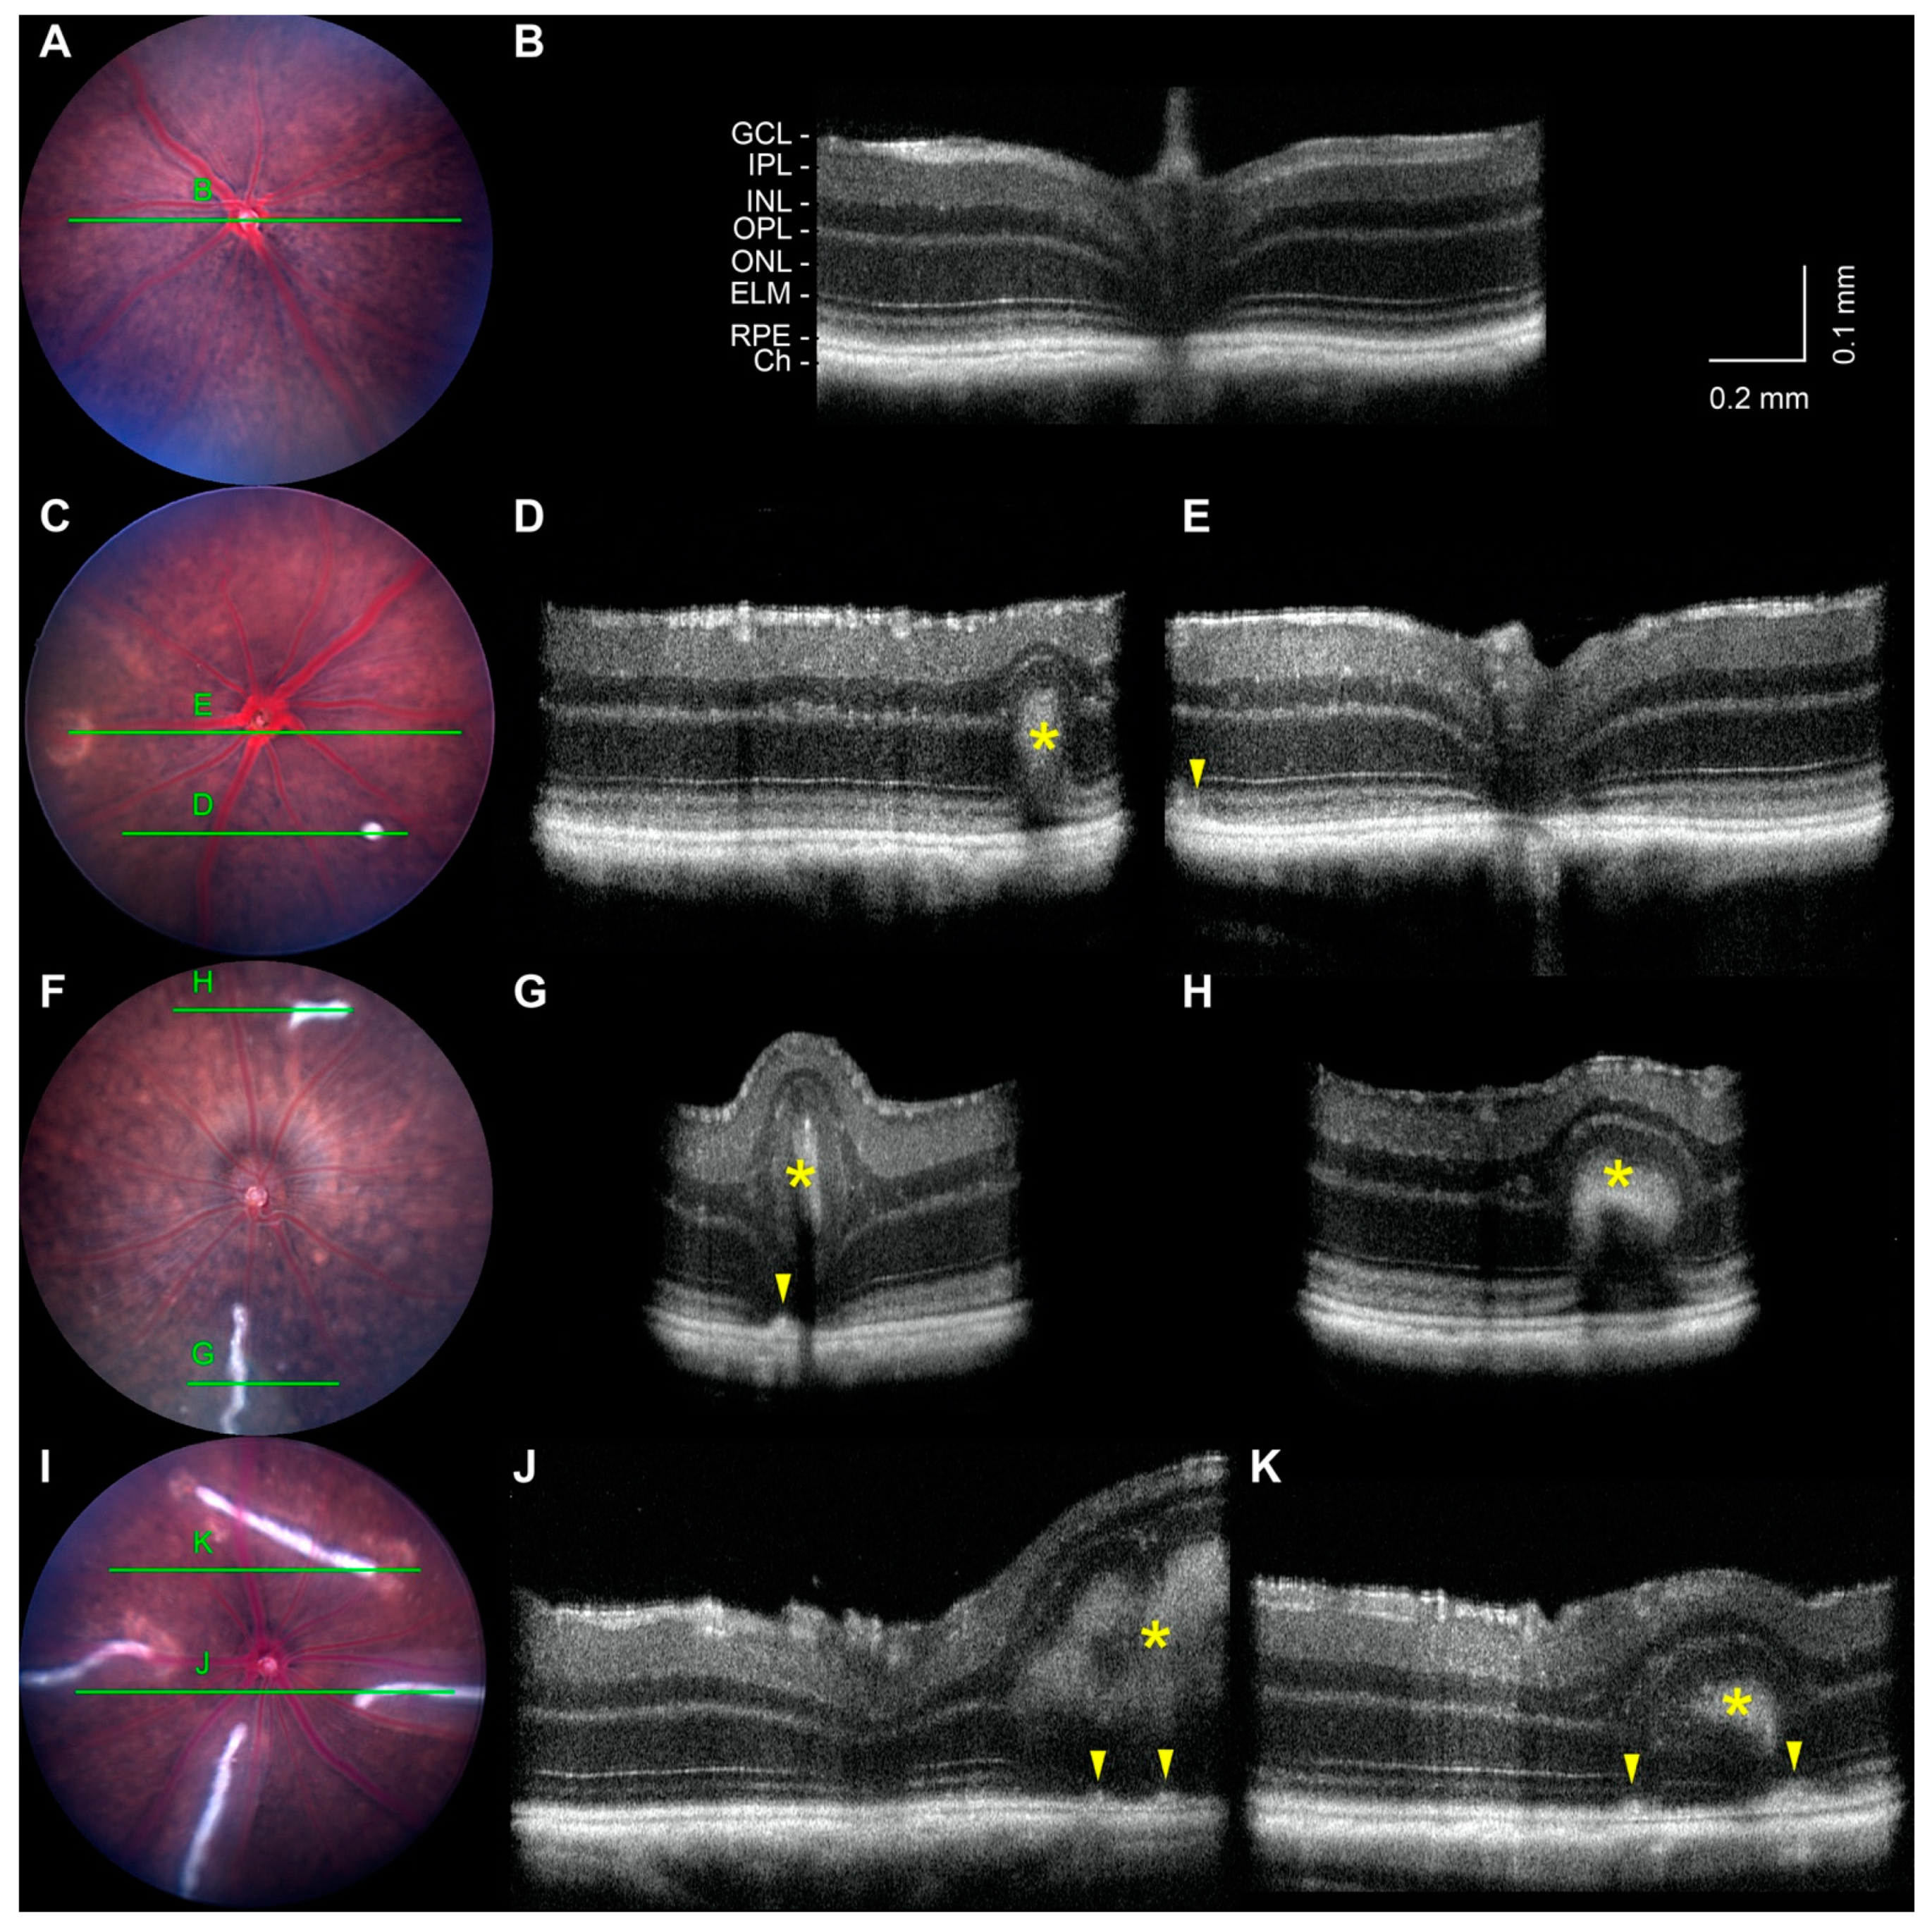

2.5. Noninvasive Imaging of White-Line Lesions and Hypopigmented Patches

2.6. Retinal Detachment and Layer Thinning